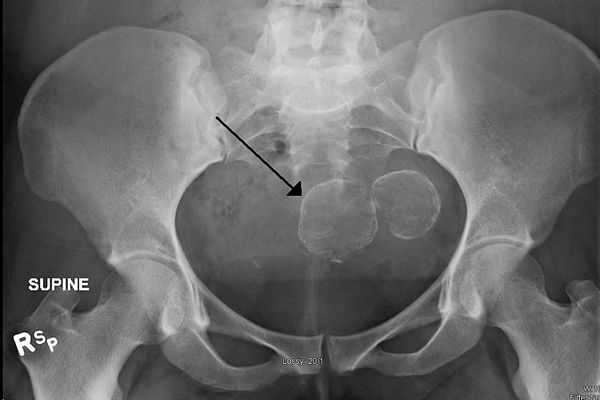

У женщин детородного возраста при наличии регулярных месячных миома может остановиться в развитии. Но уменьшиться или «рассосаться» полностью она не способна. В постменопаузе миомы могут становится меньше и даже приобретать вид кальцинатов.

Миома матки бывает единичной и множественной. От чего зависит, сколько узлов образуется, и с какой скоростью они будут расти — неизвестно. В целом динамика роста узлов непредсказуема. Кроме периода беременности, когда большая часть узлов начинает расти под воздействием прогестерона, нет ни одного научно доказанного фактора, влияющего на рост миомы матки. После наступления менопаузы миома матки подвергается обратному развитию — узлы должны начать уменьшаться в размерах, в них наступают дистрофические изменения.